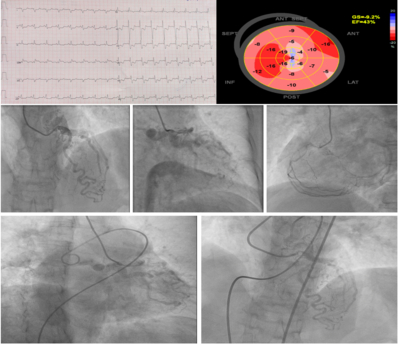

Case summary: A 62-year-old female presented with complaints of dyspnea and angina on exertion for 1 month and had paroxysmal nocturnal dyspnea for the last 4-5 days. She also had an episode of ventricular tachycardia which required DC cardioversion. She had diabetes mellitus type 2 and hypertension. ECG showed diffuse horizontal ST segment depression in precordial, and limb leads and ST segment elevation in aVR suggesting subendocardial ischemia. The echocardiogram showed hypokinesia in basal, mid-inferior and inferolateral segments and LVEF of 42%. There was a marked reduction in global longitudinal strain (average GLPS of -9.2%). Her coronary angiogram revealed extensive collaterals to the left circumflex artery (from the left anterior descending artery and right coronary artery). The left circumflex artery was arising from the pulmonary artery. Exact localization of origin was done by simultaneous contrast injections in the right pulmonary artery and LAD. The anomalous origin of LCx from the right pulmonary artery was hooked using a Tiger catheter.